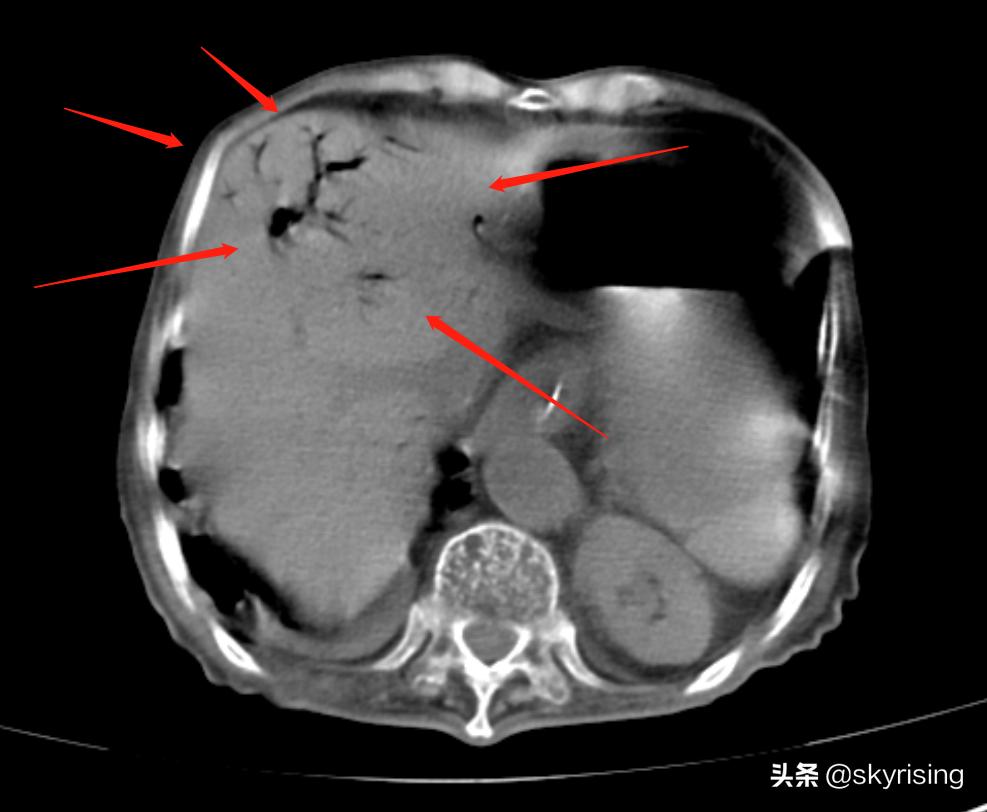

影像表现:CT平扫,红色箭头所示肝左叶见树枝状气体密度影。如果是肝内胆管积气,多半伴有肝内胆管结石或新鲜术后痕迹,且不会到达肝脏边缘。如果是门静脉积气,是伴行血管,形似树枝状,表现符合。考虑门静脉积气可能。